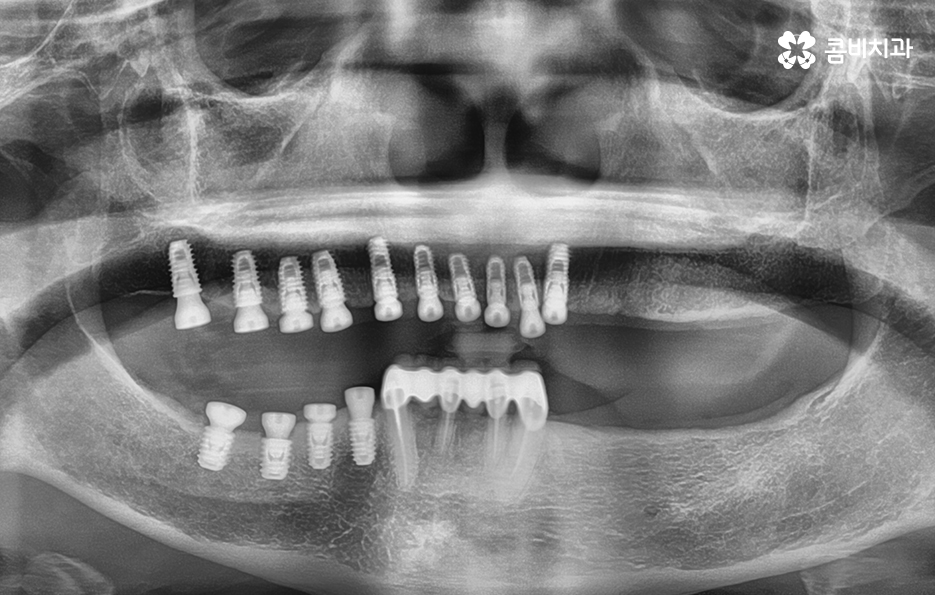

기존 치아의 색과 모양에 어울리는 보철물을 씌워서 마무리하는 과정

모든 시술이 마무리 된 상태

한국인들이 감기 다음으로 많이 겪는 질환이 잇몸질환이라는

통계가 있을 정도로 중년 이후에는 특히 잇몸질환에 대해 주의해야 합니다.

잇몸은 한번 약해지고 내려앉게 된다면 재생이 쉽지 않기 때문에

치료를 늦지 않게 받는 것이 좋고 예방에 최선을 다해야 합니다.

임플란트 시술 후에는 자연치아에 비해서 잇몸질환에

더 취약할 수밖에 없기 때문에 주기적인 스케일링과 검진을

통해서 임플란트 부작용을 예방하는 것이 오랫동안

수명을 잘 유지하고 심미성 역시 잘 유지할 수 있는 방법입니다.